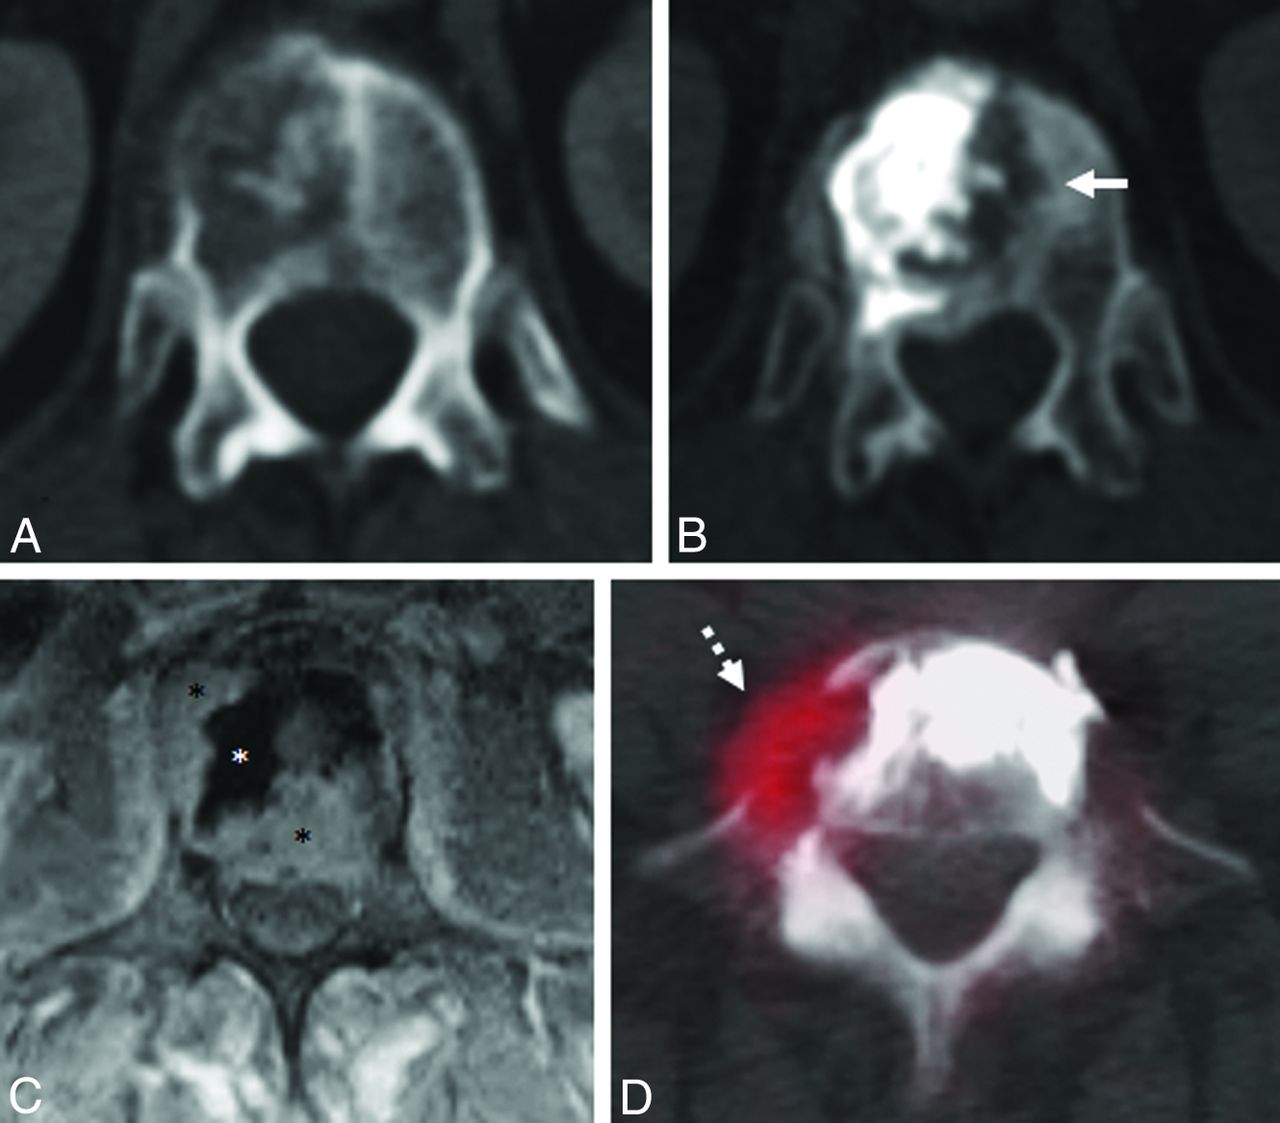

Examples of ablation failure. A, Axial CT image shows a T12 lytic squamous cell carcinoma metastasis. B, CT scan obtained 4 months after radiofrequency ablation and vertebral augmentation shows new osteolysis medial to the cement and extending across the midline (white arrow), consistent with progression of residual tumor. C, Axial postcontrast, T1-weighted, fat-suppressed MR imaging performed 6 months after radiofrequency ablation and vertebral augmentation of an L3 non-small cell carcinoma metastasis shows signal void corresponding to cement in the ablation cavity (white asterisk), with residual enhancing tumor in the right lateral and posterior vertebral body that extends into the epidural space (black asterisks). D, Axial [18F] fluorodeoxyglucose PET/CT scan obtained 1 month after radiofrequency ablation and vertebral augmentation of an L5 liposarcoma metastasis shows residual hypermetabolic tumor along the right anterolateral aspect of the vertebral body (white dashed arrow).

Of the 9 cases in which radiographic local tumor control was not achieved, the median time to documented tumor progression was 12.1 weeks (range, 3–20 weeks). Residual or recurrent tumor was present in the posterior vertebral body and/or epidural space in 89% (8/9) of cases, and in the anterolateral vertebral body in 1 case (11%; 1/9). In 89% (8/9) of cases, the ablation was performed from a bipedicular approach. In the one case in which failure occurred after a unipedicular approach, tumor recurrence occurred in the contralateral hemivertebral body (Fig 2).

One case of ablation failure occurred in the hemivertebral body contralateral to where ablation was performed (Fig 2). Although the entirety of osteolysis on pretreatment CT was confined to the right hemivertebral body and was accessible from a right unipedicular approach, microscopic tumor infiltration into the left hemivertebral body was presumably beyond the margin of the ablation zone. As a result of this case, our current practice is to ablate the entire volume of T2-hyperintense marrow signal and enhancement on MR imaging, or the entire volume of FDG avidity within the vertebral body on PET/CT, as well as an additional 3-mm margin to account for microscopic tumor infiltration.16